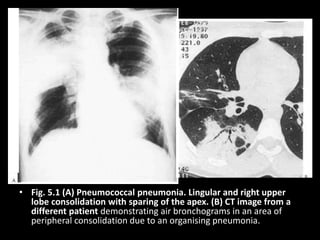

• Fig. 5.1 (A) Pneumococcal pneumonia. Lingular and right upper

lobe consolidation with sparing of the apex. (B) CT image from a

different patient demonstrating air bronchograms in an area of

peripheral consolidation due to an organising pneumonia.

• Fig. 5.1(A) Pneumococcal pneumonia. Lingular and right upper lobe consolidation with sparing of the apex. (B) CT image from a different patient demonstrating air bronchograms in an area of peripheral consolidation due to an organising pneumonia.